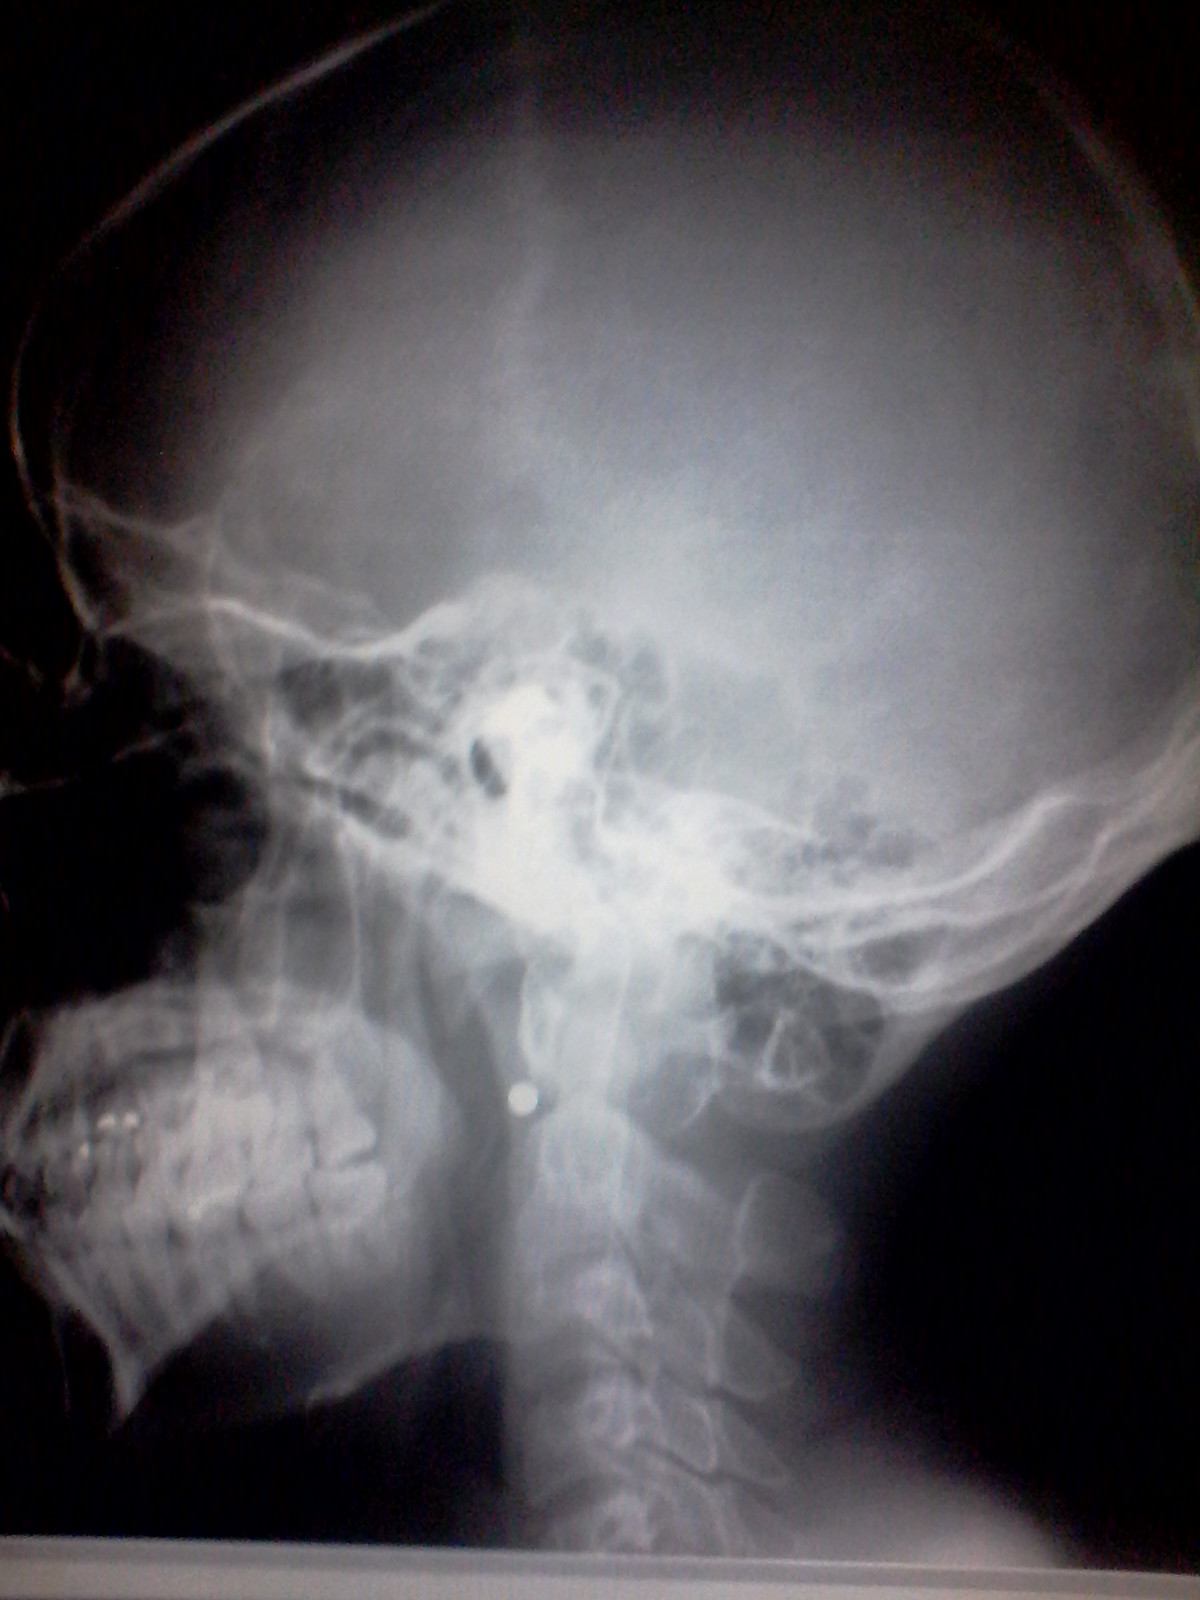

Les cuento que la imagen que acaban de observar es de una persona ya difunta y no, la persona no murió luego del estudio, al contrario, le realizamos el estudio ya muerto y esto, amigos míos, es algo mas común de lo que pueden pensar.

Uno que otro día a la semana suelen ingresar cadáveres a la sala de rx en el Hospital Central Dr Pacido D. Rodriguez, en la mayoría de los casos, con el fin de encontrar algún proyectil que se haya movido luego del impacto migrando a otra parte del cuerpo.

Ahora bien, esto no es algo normal, al menos no en todo el mundo. Un equipo de Rx, aunque es muy útil, es extremadamente costoso así como su mantenimiento, y para nadie es un secreto la precaria situación de mi país, Venezuela, lo que ha traído también como consecuencia el deterioro de los equipos de rx utilizados en las oficinas de criminalistica, haciendo que el personal de esta área se vea en la necesidad de trasladar al cadáver hasta los centros hospitalarios mas cercanos para poder realizar el estudio.